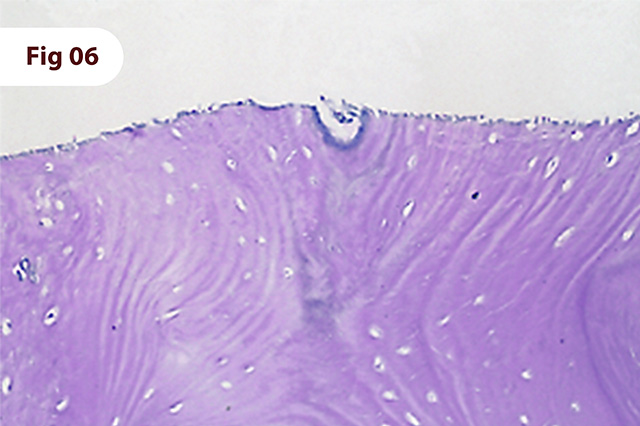

Exame histológico do bloco ósseo removido. Aumento de 20x. Regeneração óssea completa com ausência do biomaterial (OIB) utilizado como estabilizante do coágulo.